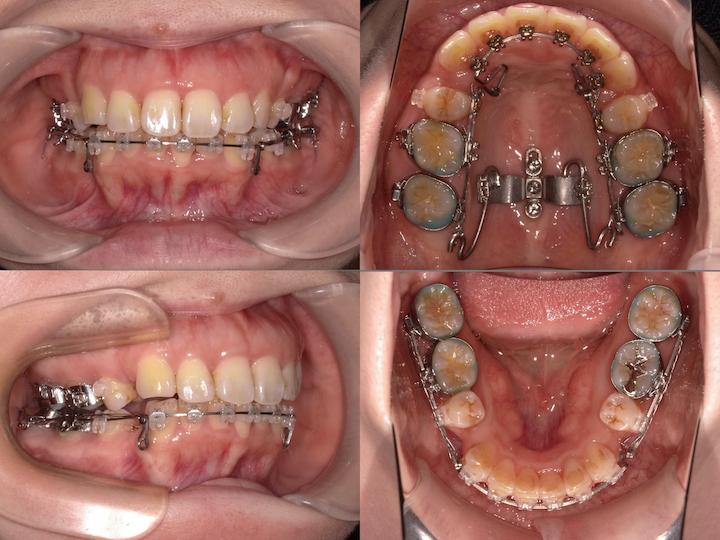

初診時年齢33歳5ヶ月の患者様です。口の閉じ辛さと歯の重なりを主訴にご来院されました。

上下左右4番を抜歯してアンカースクリューで上顎6番を遠心移動しながら前歯を後方に牽引しました。

さらに上顎大臼歯を圧下(上方向に移動)して下顎骨の前上方への回転を促しました。

本症例は前歯の移動量が大きいことから上顎前歯が切歯孔にぶつかるリスクがあります。初診時とアンカースクリュー埋入時のCTデータから歯根の位置を確認しながら上顎前歯の後方移動を行いました。